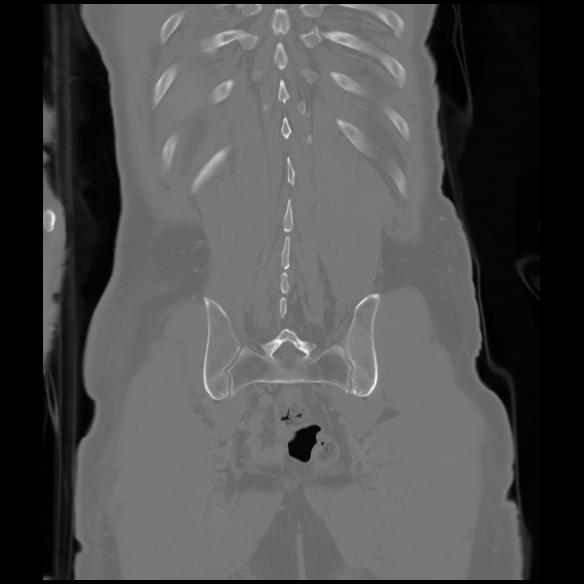

6 CUERPO,CE,Coronal,3.000,CUERPO,Coronal,